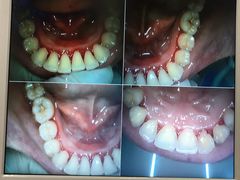

• 牙博士口腔品牌连锁(杨浦店)

• -牙博士口腔品牌连锁(杨浦店)

dd | 21-07-22

沐夏 | 21-07-22